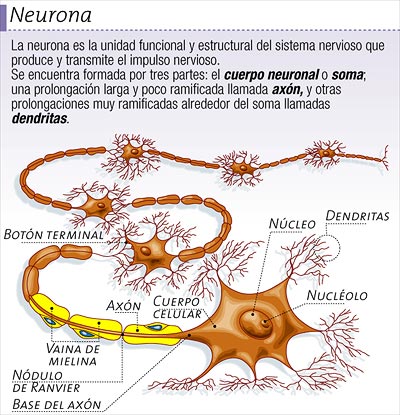

Si nos paramos a pensar en el hecho cierto de que, el cerebro humano adulto, con poco más de un kilo de peso, contiene unos cien mil millones de células nerviosas o neuronas, La capa ondulada más exterior o corteza cerebral, que es la parte del cerebro de evolución más reciente, contiene alrededor de 30 mil millones de neuronas y más de un billón de conexiones o sinapsis. Si contaramos una sinapsis cada segundo, tardaríamos 32 millones de años en completar el recuento. Si consideramos el número posible de circuitos neuronales, tenemos que habérnosla con cifras hiper-astronómicas: 10 seguido de un millón de ceros. No existe en el Universo ninguna otra cosa de la que pueda resultar una cantidad igual. Incluso el número de partículas del universo conocido es de 10 seguido de tan sólo 79 ceros. En comparación con el número de circuitos neuronales…¡No es nada!

El impulso nervioso viaja a lo largo del axón de la célula del cerebro, a través del espacio sináptico a otra célula del cerebro y así sucesivamente. Cuando una neurona se activa a otra de esta manera, es como si un interruptor se encendiera. Las neuronas se encienden, como una línea de fichas de dominó cayendo. Esta actividad es el proceso que crea el camino del pensamiento complejo, llamado también trazas de la memoria o caminos neuronales.

El impulso nervioso viaja a lo largo del axón de la célula del cerebro, a través del espacio sináptico a otra célula del cerebro y así sucesivamente. Cuando una neurona se activa a otra de esta manera, es como si un interruptor se encendiera. Las neuronas se encienden, como una línea de fichas de dominó cayendo. Esta actividad es el proceso que crea el camino del pensamiento complejo, llamado también trazas de la memoria o caminos neuronales.

Las neuronas de las que existen una gran variedad de formas, poseen unas proyecciones arborescentes llamadas dendritas mediante las cuales realizan las conexiones sinápticas. posee así mismo una proyección única más larga, el axón, que establece conexiones sinápticas con las dendritas o directamente con el cuerpo celular de otras neuronas. Nadie ha contado con precisión los diferentes tipos de neuronas del cerebro, pero uhna estima groso modo de unos cincuenta tipos seguramente no sería excesiva. La longitud y patrones de ramificación de las dendritas y el axón de un tipo determinado de neurona caen dentro de un rango de variación determinado, pero incluso dentro de un mismo tipo, no existen dos células iguales.